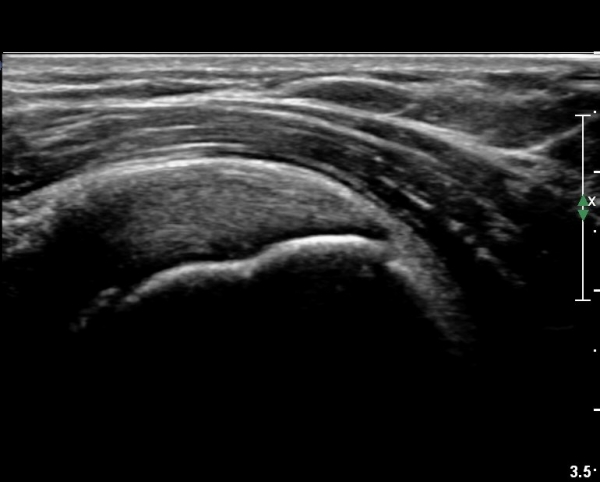

ÃÊÀ½ÆÄ °Ë»ç

´ë°áÀý°ú °ßºÀÇϺο¡ ¹æ»ç¼± Åõ°ú¼º °¨¼Ò(sclerosis)°¡ °üÂûµÈ´Ù(÷ºÎÆÄÀÏ).